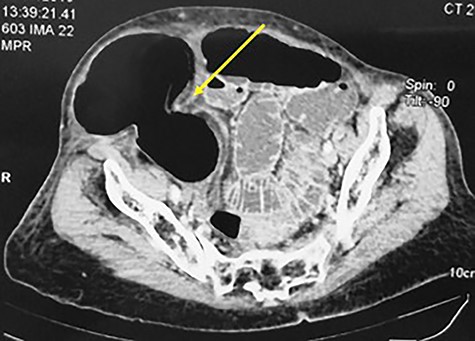

An 84-year-old patient, gravida 8, para 8, consulted in emergency department for abdominal pain and vomiting evolving for 7 days. The blood pressure was 120/70 mm Hg with a fever at 38.6°. The physical examination found an ovoid non-reducible mass of the right lower quadrant (Fig. 1). There was no abdominal tenderness or peritoneal signs. The computed tomography (CT) scan showed a strangulated right spigelian hernia with a hernial ring measured to 3.4 cm. The content was the coecum (Fig. 2). There were also signs of bowel ischemia with pneumatosis and minimal peritoneal effusion (Fig. 3). Biology found leukocytosis at 15 200 elements per mm3. Surgical exploration with an incision centered on the mass confirmed the diagnosis. There was an extensive necrosis of the hernial sac and its contents (the caecum, appendix and 10 cm of the terminal ileum) (Figs 4 and 5). A right hemi-colectomy with an ileo-colic anastomosis was performed. The parietal defect was closed by an aponeurorraphy with Mersuture 0. The post-operative course was marked by the death of the patient in intensive care due to multi-visceral failure.

CT scan showing a strangulated right spigelian hernia with hernial ring (arrow) measured at 3.4 cm the coecum as content.